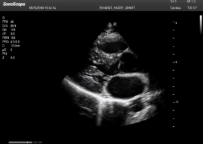

不同的探頭對應(yīng)于不同的臨床領(lǐng)域,不同的探頭頻率也應(yīng)用于不同的人體組織。超聲波在人體中的衰減與探頭頻率有關(guān),探頭頻率越高,穿透力越弱,分辨率越高,而探頭頻率越低,穿透力越強(qiáng),分辨率越低。因此在檢查淺表器官時應(yīng)選用高頻探頭,而檢查深部臟器時則選用穿透性強(qiáng)的低頻探頭。